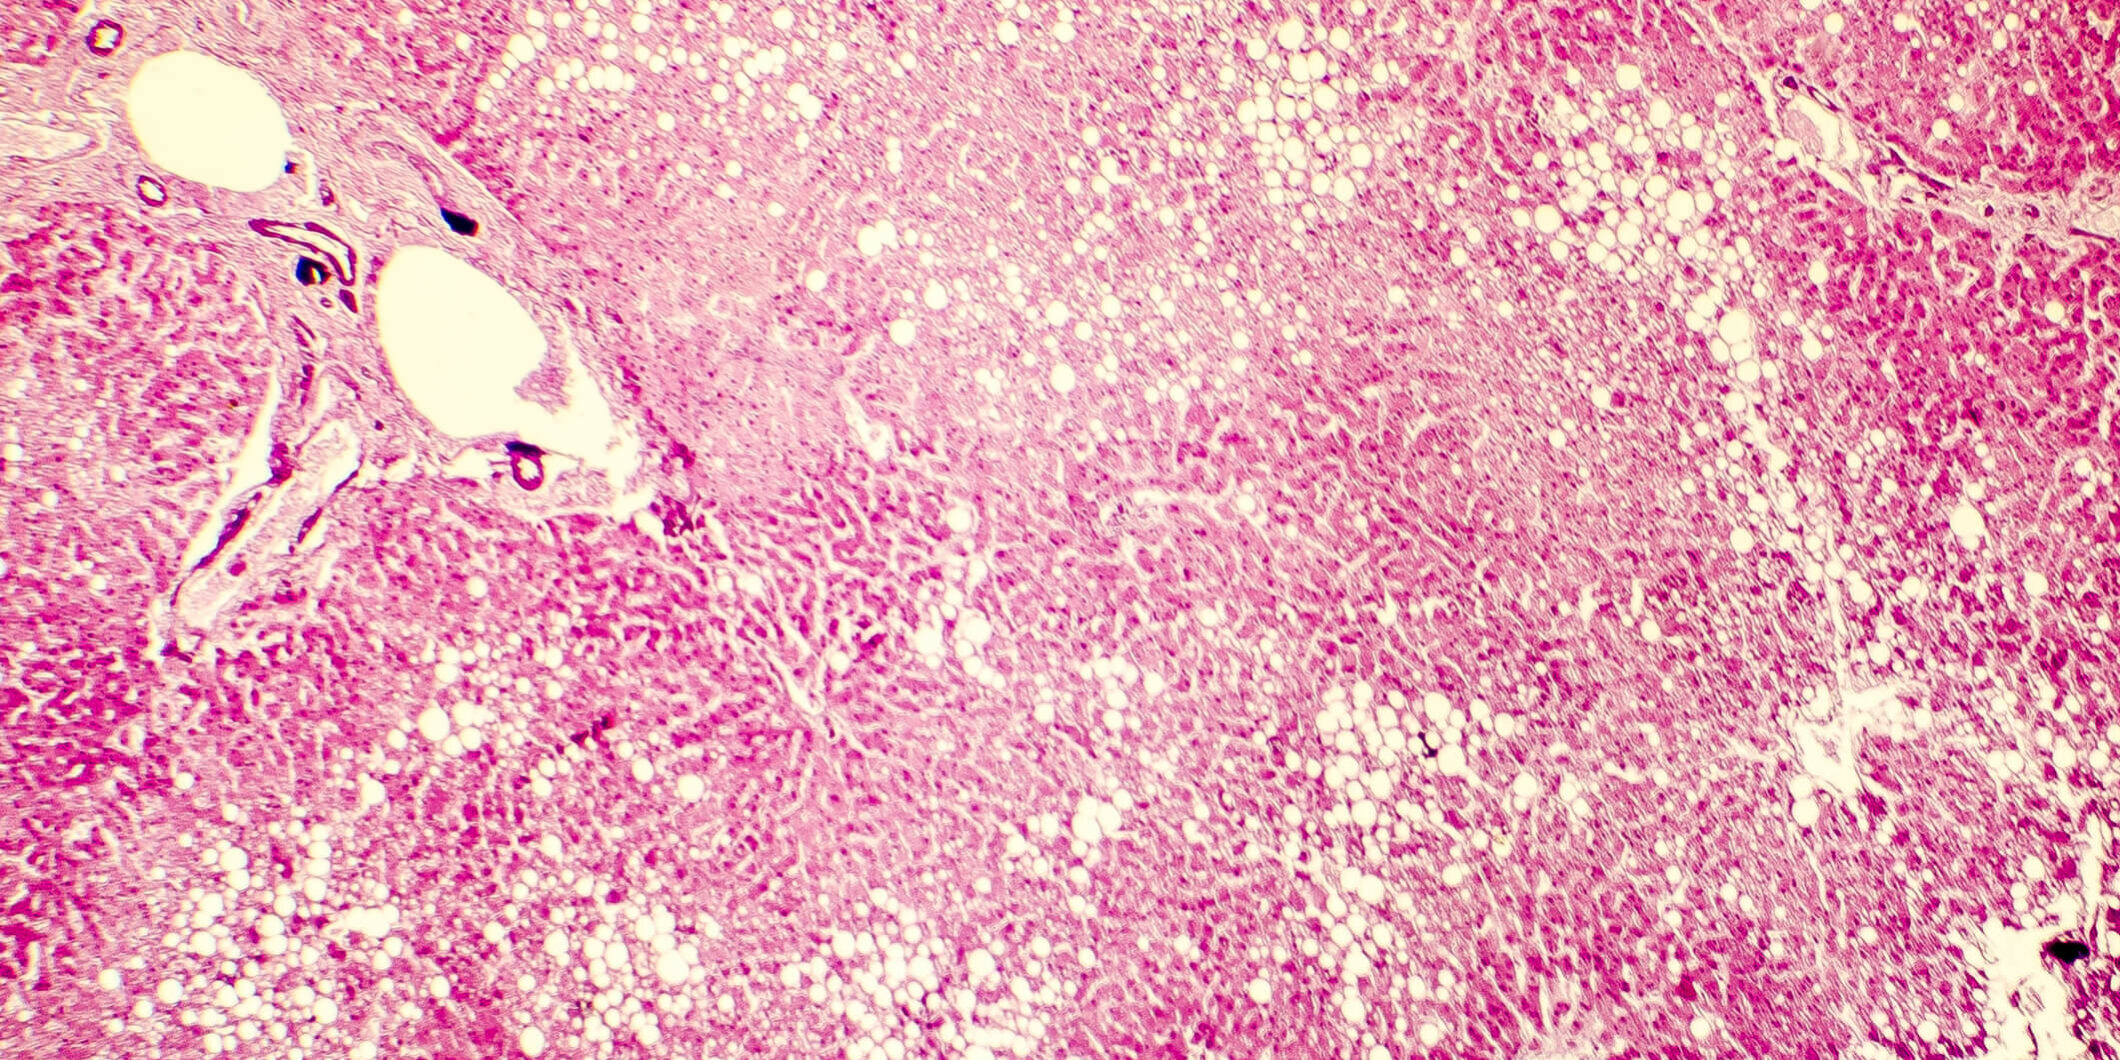

Stukovatená pečeň – odborne steatóza vzniká ako dôsledok ukladania nadmerných zásob tuku.Pečeň filtruje všetky látky, ktoré telo prijíma. Jej primárnou funkciou je rozdeľovať ich medzi orgány a vytvárať zásoby. Pokiaľ prijímate veľké množstvo tuku, ktorý nevie efektívne zužitkovať, pečeň ho začne ukladať v iných orgánoch aj priamo v sebe. A to je veľký problém, nakoľko tuk je pre pečeň toxický. Vyvoláva zápal a spôsobuje odumieranie jej buniek – dochádza k poruche základnej funkcie orgánu. Najväčším rizikom stukovatenej pečene je, že môže prerásť do veľmi závažných ochorení ako fibróza alebo cirhóza pečene.

Ako liečiť stukovatenú pečeň? V prvom rade je nutné navštíviť odborníka, ktorý prehmataním a postláčaním brucha zistí, či je pečeň zväčšená. Dôležité sú krvné testy, v rámci ktorých sa skúmajú látky ALT (alanínaminotransferáza) a AST (aspartátaminotransferáza) – ide o pečeňové enzýmy. Ak sú zvýšené, môže to indikovať zápal pečene. Lekár môže nariadiť aj iné vyšetrenia ako sono pečene, CT, prípadne magnetickú rezonanciu. V závažnejších prípadoch sa vykonáva biopsia pečene.